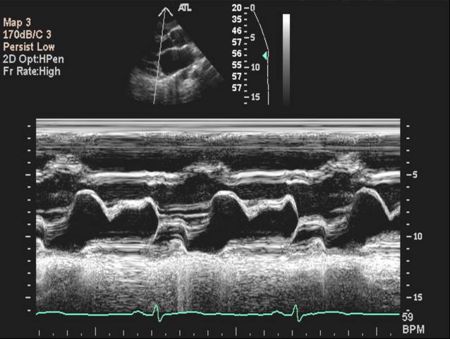

Mitral Valve M-mode Analysis

- Anterior leaflet with E/A appearance of diastology

- Decreased EF slope in MS

- Scalloping of leaflet tip in end systole in prolapse